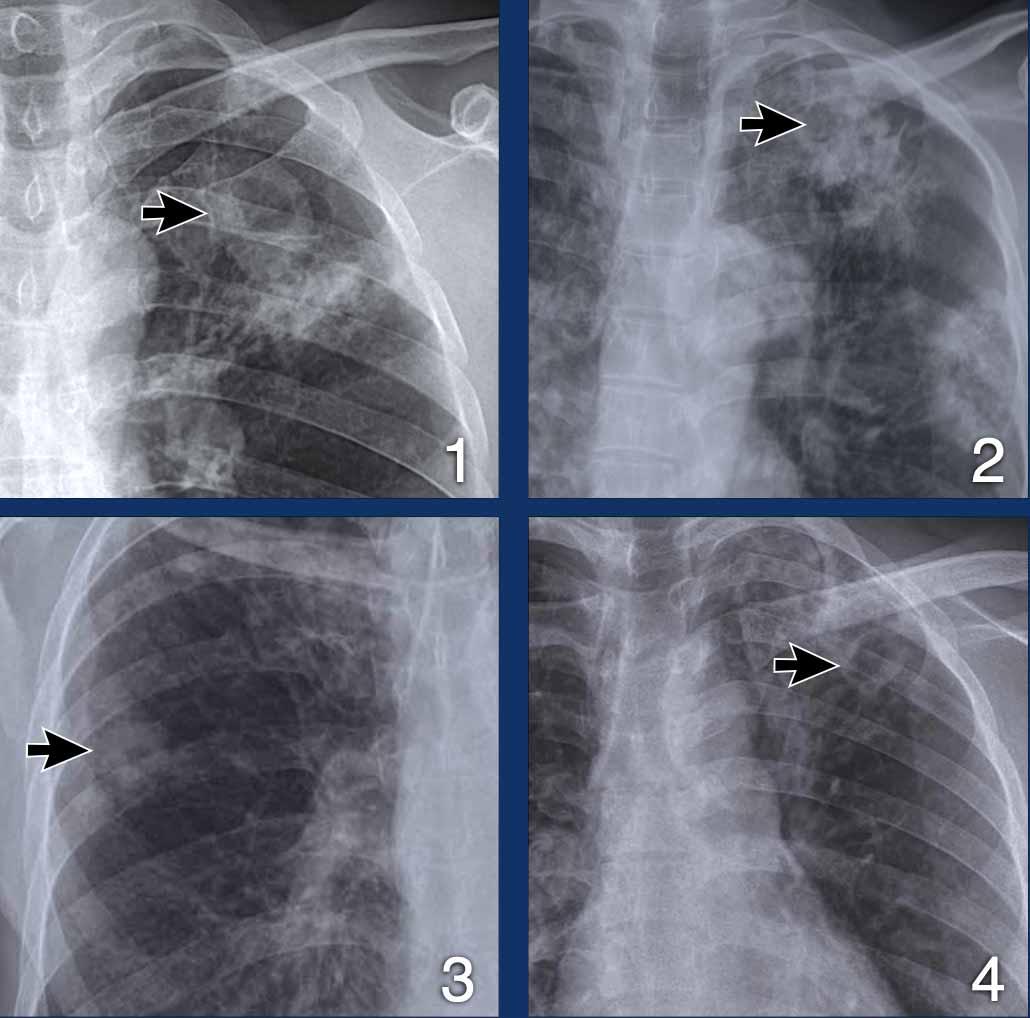

Hình ảnh

- Đông đặc thùy trên và tạo hang.

- Đông đặc đậm với tạo hang kín đáo (mũi tên).

- Hang nhỏ thành dày.

- Tạo hang thùy trên trái.

Tất cả các bệnh nhân này đều được xác nhận lao bằng xét nghiệm vi sinh.